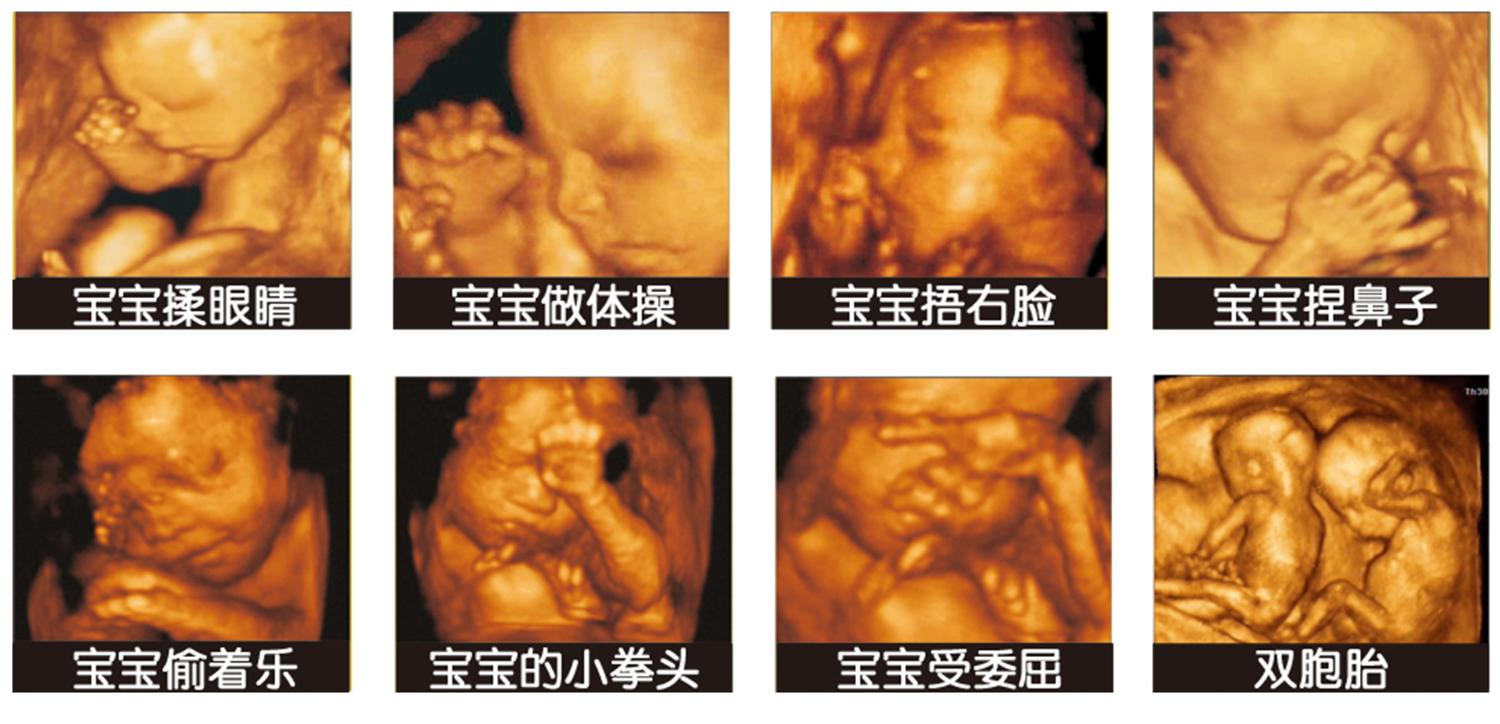

四维彩超是目前最为先进的彩色超声设备,简单点说就是把原有的二维彩超的图片通过软件加工成立体图像,这样能够提高诊断的准确率。

其实以实际情况来看,很多准妈妈之所以愿意做四维彩照,最主要还是想看看胎儿的模样,看看胎儿在子宫里是如何活动的,因此也有一些人会将四维彩超称之为“子宫内写真集”。

这个时候宝宝还在发育的阶段,根本没有发育完全,而且此时的胎儿浑身都的胎脂,这样四维彩超拍出来的时候,也只能排到大概轮廓。

我们拍照片的时候还需要摆个姿势才会好看,胎儿在妈妈肚子里只能保持卷曲的状态,而一般拍摄四维彩照的时候,医生主要还是为了排畸,也就会容易忽略拍摄角度的问题。

四维彩超只是一个大概影像,它不可能像照相机一样拍摄的特别清晰,也不能捕捉到胎儿的各种细节部位,而且在最后医生还会对个部位进行放大,这样就会出现胎儿大嘴巴大鼻子的情况。